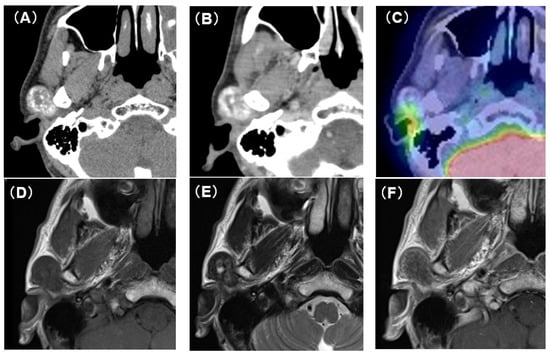

Computed tomography (CT) showed an oval tumor in the region of the right TMJ, extending to the upper pole of the parotid gland. The tumor was oval-shaped with an actual width of 2.5 cm and a length of 3 cm. It had well-defined borders and a diffuse hyper-absorptive zone within, which indicated diffuse calcification (Figure 1A,B). Positron emission tomography with 18F-fluorodeoxyglucose (18F-FDG-PET) showed a mild uptake of 18F-FDG (SUVmax = 3.25) (Figure 1C). There was no uptake in other sites except for physiological uptake. The tumor showed a poor contrast effect with iodine-based contrast medium. A magnetic resonance image (MRI) showed a well-defined mass in the upper pole of the right parotid gland. T1-weighted images showed a low-signal tumor (Figure 1D), while T2-weighted images showed a low-signal tumor with a macular high-signal area (Figure 1E). The contrast effect of gadolinium was poor (Figure 1F). Fine-needle aspiration cytology confirmed only neutrophils and histiocytes; there were no definitive findings.

Figure 1. CT, PET-CT, and MRI findings. (A) Plain CT horizontal section. The inside of the tumor is diffusely accompanied by a high-density area. (B) Contrast-enhanced CT horizontal section. The contrast enhancement effect of the tumor is poor. (C) PET-CT image findings. The tumor showed mild uptake of 18F-FDG (SUVmax = 3.25). (D) Plain MRI T1 image findings. The tumor is visualized as an area of uniform low-intensity. (E) Plain MRI T2 image findings. Low-intensity mass lesion with faint patchy hyperintensity inside. (F) Contrast-enhanced MRI T1 image findings. The tumor enhancement with gadolinium was poor.